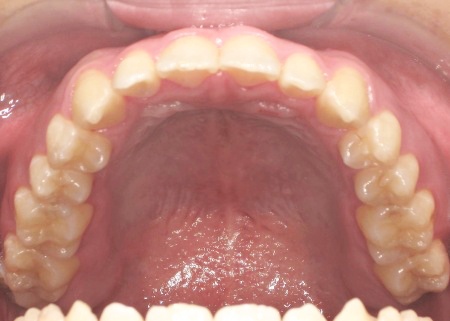

最後に、歯並びと噛み合わせが整い、見た目にも問題がないことを確認し、治療を終了しています。